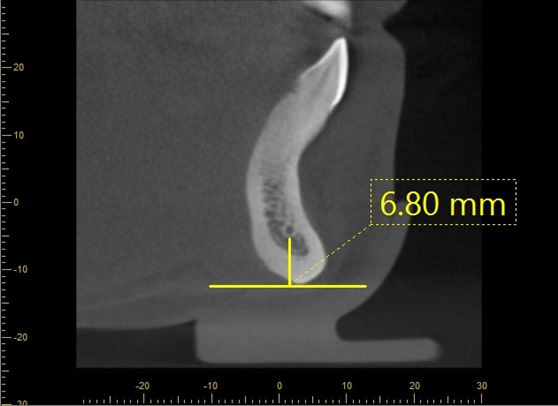

Methods: Retrospective study of 120 CBCT images in the anterior mandible were performed. All CBCT images were obtained with 3D Accuitomo (J. Morita Mfg. Corp., Kyoto, Japan) with the exposure setting of 80-90 kVp, 4-5 mA, 18 s., and FOV 10×10 cm with voxel size of 0.25 mm. The assessment of the visibility of the MIC will be recorded the detection frequencies and analyzed into the percentage. For linear measurement, the CBCT images will be analyzed from the curvedMPR. The cross-sectional images that pass through the midline, 5 mm, 10 mm, 15 mm, 20 mm from the midline (both right and left sides) will be selected and measured with the digital ruler from the viewer (i-dixel) equipped with the CBCT machine. All images will be measured in the following distances: Incisive canal to the inferior border of mandible (L1), Incisive canal to buccal plate of mandible (L2), Incisive canal to lingual plate of mandible (L3), Bucco-lingual diameter of outer contour of MIC (D1), Vertical diameter of outer contour of MIC (D2).

Results: The MIC was identified in 96% of the CBCT images. Mean (s.d.) distance from MIC to inferior border of mandible at midline, 5 mm, 10 mm, 15 mm, 20 mm from the midline were 8.74 (1.61) mm, 9.80 (1.37) mm, 10.21 (1.12) mm, 10.13 (1.89) mm, 11.03 (1.56) mm, respectively. Mean (s.d.) distance from MIC to buccal border of mandible were 4.17 (1.41) mm, 3.86 (1.28) mm, 3.74 (1.19) mm, 3.24 (1.03) mm, 3.18 (1.31) mm, respectively. Mean (s.d.) distance from MIC to lingual border of mandible were 4.02 (1.17) mm, 3.46 (1.06) mm, 3.54 (1.62) mm, 3.29 (1.47) mm, 3.84 (1.71) mm, respectively. Mean (s.d.) buccolingual diameter were 1.78 (0.37) mm, 1.97 (0.52) mm, 2.10 (0.40) mm, 2.25 (0.73) mm, 2.86 (0.51) mm, respectively. Mean (s.d.) vertical diameter were 1.84 (0.37) mm, 1.91 (0.49) mm, 2.53 (0.38) mm, 2.92 (0.46) mm, 3.11 (0.43) mm, respectively.